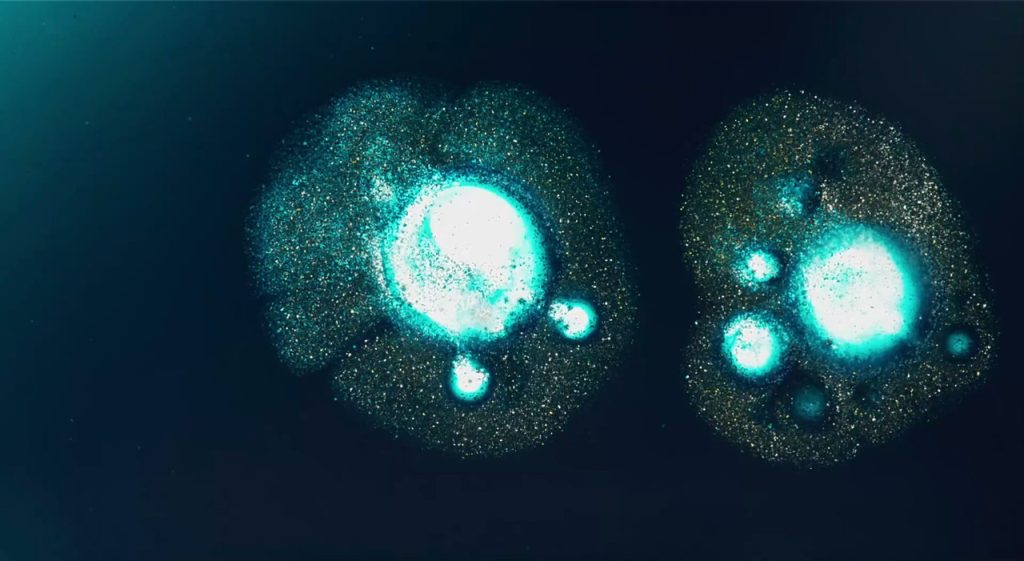

Pubblicata sulla rivista scientifica ACS Nano, questa ricerca ha messo in luce, per la prima volta, le alterazioni morfologiche e spaziali dei lisosomi in modo quantitativo e tridimensionale. I ricercatori si sono concentrati sulla malattia di Niemann-Pick tipo C1 (NPC1), un disturbo causato da difetti negli enzimi lisosomiali, che portano a gravi problemi metabolici e a esiti spesso letali.

Grazie all’innovativa tecnologia della tomografia olografica in configurazione citometrica a flusso (HTFC), i ricercatori hanno potuto misurare diversi parametri biofisici dei lisosomi, come densità e volume. Hanno scoperto, ad esempio, come l’accumulo di varie molecole possa alterare le proprietà fisiche dei lisosomi, consentendo di differenziare le cellule sane da quelle affette da NPC1. Questa innovazione apre nuove strade per monitorare gli effetti di terapie farmacologiche e genetiche, nonché per identificare biomarcatori nuovi e specifici per le malattie da accumulo lisosomiale.

Uno dei principali vantaggi della metodologia HTFC è la sua capacità di analizzare migliaia di cellule in sospensione senza necessità di complessi preparativi. Questo potenziale porta a studi più realistici rispetto ai modelli tradizionali basati su cellule adese. Ad esempio, un’analisi su larga scala delle cellule di pazienti potrebbe rivelare dati cruciale sulla progressione delle malattie lisosomiali.

I ricercatori intendono ora validare l’approccio su cellule prelevate da pazienti e migliorare la risoluzione della tecnologia per consentire l’osservazione di singoli lisosomi. Questo stadio di avanzamento avvicinerebbe ulteriormente la nuova tecnica alle capacità della microscopia ad alta risoluzione, mantenendo però il vantaggio dell’analisi statistica su larga scala.